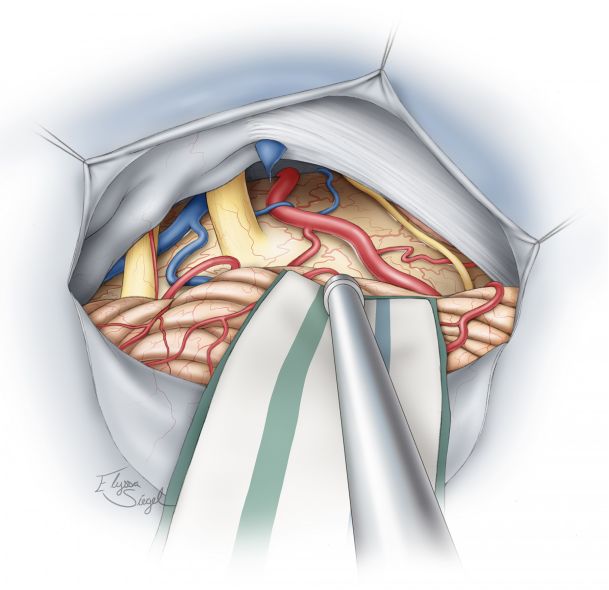

图12. 切除肿瘤后可见后颅窝的解剖,如图显示了乙状窦后和小脑上入路的手术通道。